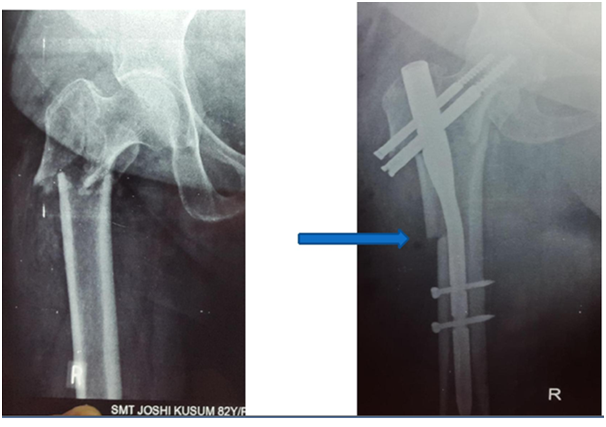

4. Often has 2 Screws in head.  Lag screw and hip pin.  Controls rotation well (Figures 2 & 3).

Figure 2 PFN Biomechanically stronger than DHS.

Figure 3 Excessive collapse with DHS within first week. ?Due to lateral wall comminution.